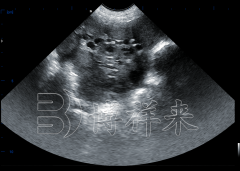

新手使用牛用B超机如何区分母牛子宫、膀胱和瘤

在牛场繁殖管理和疾病检测中,牛用B超已经成为不可或缺的工具。然而,对于刚接触设备的新手来说,最常见的难题之一就是在实际操作中无法准确区分子宫、膀胱和瘤